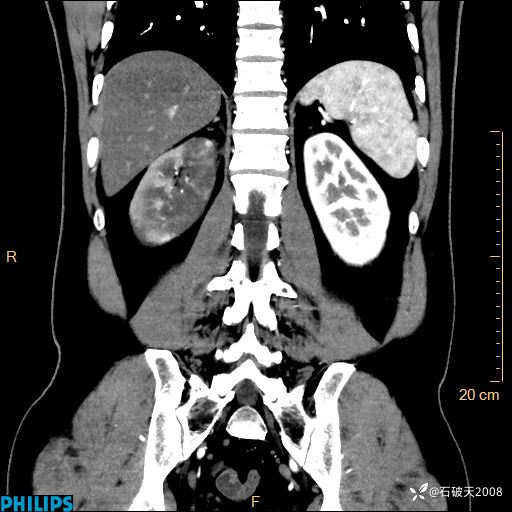

这个病例诠释了“腹部不增强,等于耍流氓”

男 44岁 主 诉:右侧腰背部疼痛4天。

现病史:4天前无明显诱因出现右侧腰背部疼痛,呈阵发性发作,疼痛性质描述不详,无尿频、尿急、尿痛,无恶心呕吐、腹泻、黑便,无胸闷、胸痛、呼吸困难,无发热、寒颤等,休息后缓解不明显,昨日到我院门诊就诊,行泌尿系彩超示:1.双肾肾砂;2.前列腺体积稍大。予“肾石通丸”、“左氧氟沙星片”等药物口服治疗后无缓解,昨日夜间再次到我院就诊,急诊科予“复方双氯芬酸钠注射液”肌注处理后好转,今晨仍感右侧腰背部疼痛,再次来诊并由门诊以“腰痛”为初步诊断收入我科。发病来患者神志清,精神稍差,饮食睡眠欠佳,小便正常,大便不畅,体重近期无下降。

冠状位